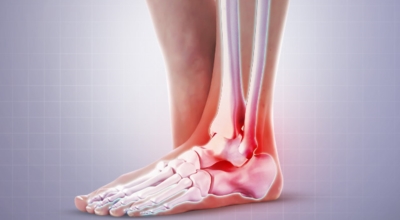

주요 증상은 통증으로 발뒤꿈치 안쪽이 아주 아프며, 맨발로 바닥을 걸을 때 걸음을 내딛을 때마다 통증이 있어요. 가장 심한 통증은 아침에 일어나 첫 걸음을 뗄 때인데, 밤에 족저근막이 수축하다가 발에 체중이 가해지면서 갑자기 늘어나는 현상입니다.